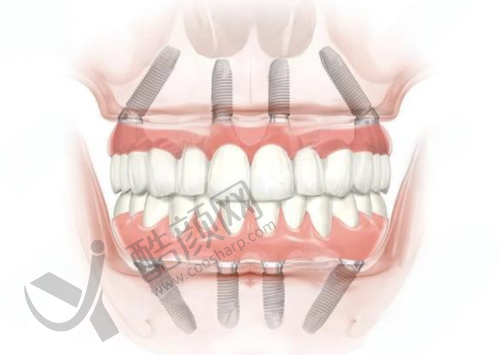

大家都知道,种植牙是一项技术活,它可不是简单的事情。正常情况下,一颗种植牙的价格跨度比较大,从几千元到上万元都有。毕竟,种植牙涉及到种植体、牙冠、手术费、检查费等多个方面的费用。

一般来说,种植体的品牌不同,价格也会有较大差异。一些有名进口品牌的种植体,由于其质量和稳定性较好,价格自然就高。而牙冠的材质也有多种选择,比如烤瓷牙冠、全瓷牙冠等,不同材质价格也不一样。手术费则和医生的技术水平、手术的复杂程度有关。检查费包括口腔CT、X光等,这些都是确保手术顺利进行的必要环节。